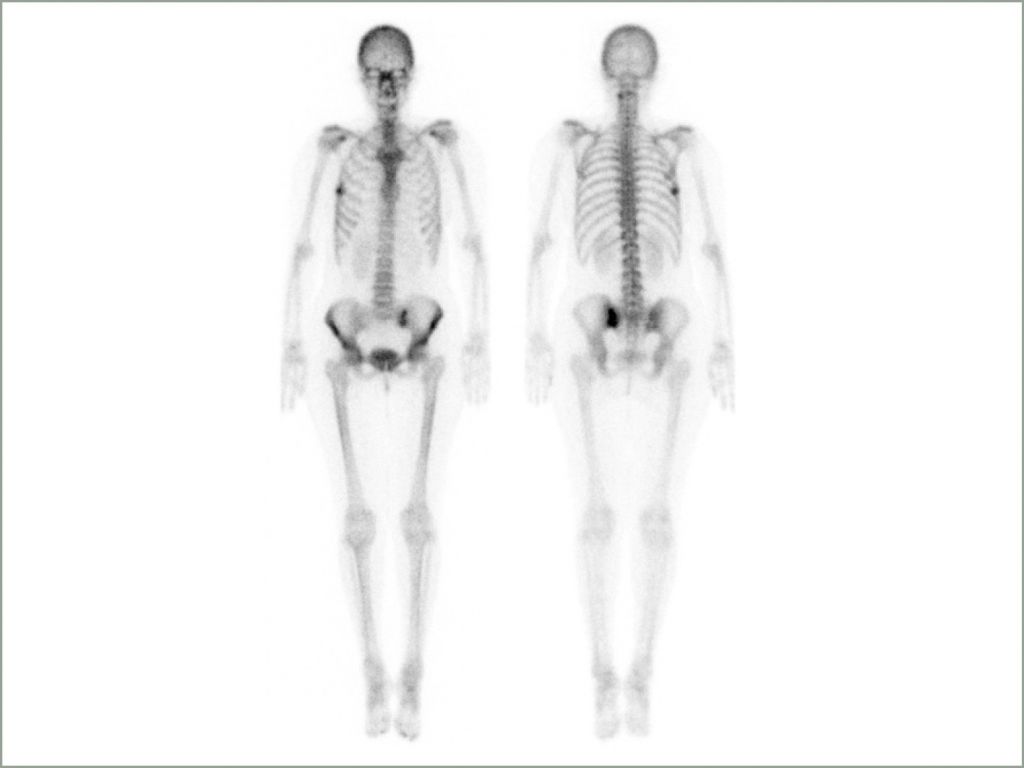

Gammakamera für SPECT-, Ganzkörper- und planare Bildgebung bei hohem Patientendurchsatz

whole body

- Dual-Intensity Darstellung von dorsal und ventral Aufnahmen

- Iliosakralgelenk-Auswertung direkt im Ganzkörperscan

- Dekonvolution Filter zum Glätten und Entrauschen der Bilder